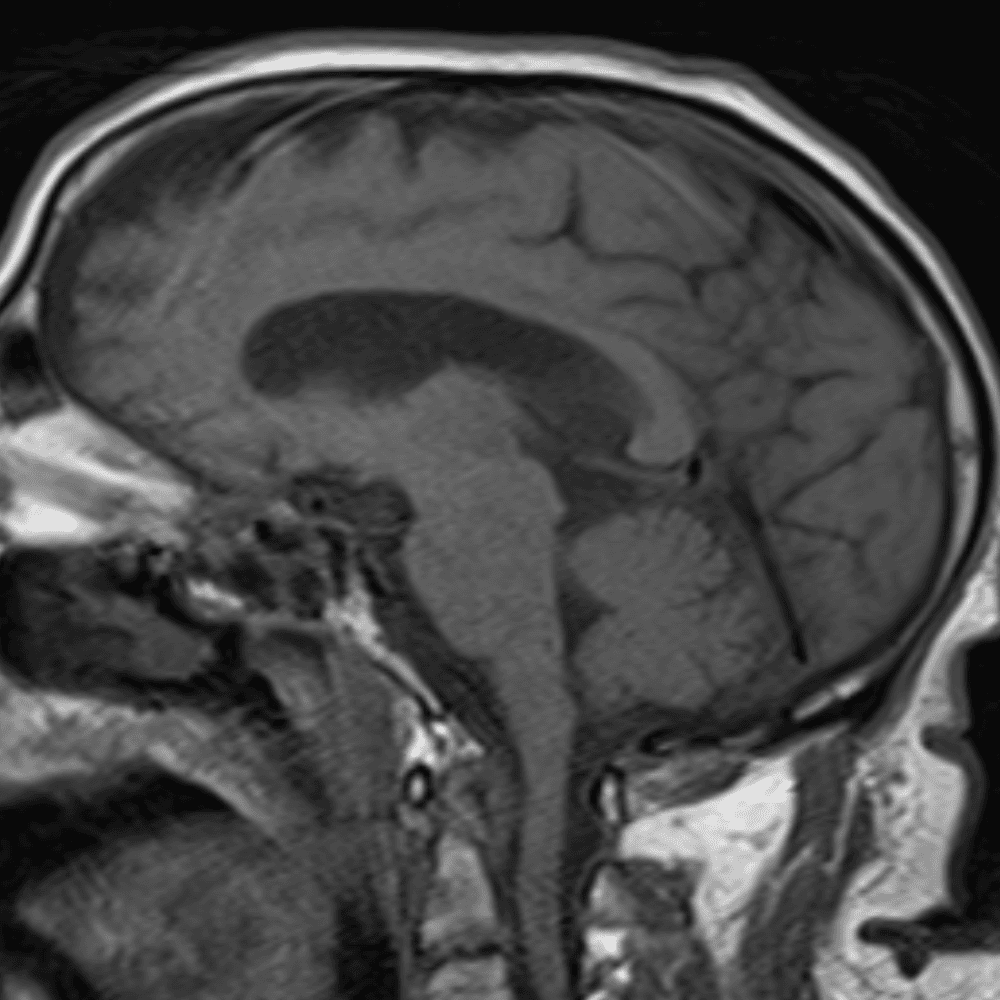

๋‹น์ง ์‹œ ํ”ํžˆ ๋ณผ ์ˆ˜ ์žˆ๋Š” ์‚ฌ๋ก€์˜ ์ „ํ˜•์ ์ธ ์˜ˆ๋ฅผ ํฌํ•จํ•ฉ๋‹ˆ๋‹ค.

39 ์‚ฌ๋ก€

์—ฐ์Šต

๋ฏธ๋ฌ˜ํ•˜๊ฑฐ๋‚˜ ์–ด๋ ค์šด ์‚ฌ๋ก€์™€ ์ผ๋ถ€ ์ •์ƒ ์‚ฌ๋ก€๋ฅผ ํฌํ•จํ•˜์—ฌ ๋‹น์ง์„ ์‹œ๋ฎฌ๋ ˆ์ด์…˜ํ•ฉ๋‹ˆ๋‹ค.

50 ์‚ฌ๋ก€